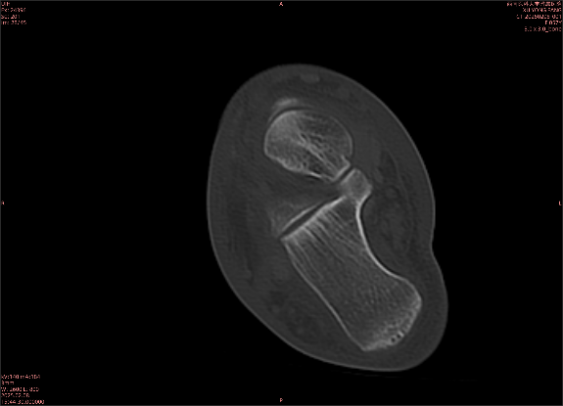

举例图像

图1

专业解释看不懂没关系,大家看图1和图2就可以了,这是同一个患者跟骨的磁共振和CT图像,图1的红色箭头指示的黑线就是磁共振图像显示的骨折线,一目了然。而对比图2的CT图像上并未显示异常。